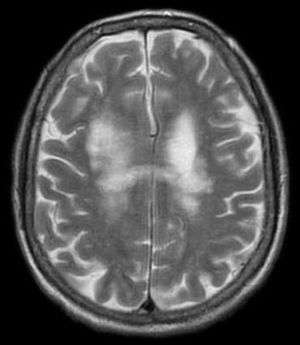

| T2-weighted MRI showing progressive multifocal leukoencephalopathy | |

PML is diagnosed in a patient with a progressive course of the disease, finding JC virus DNA in spinal fluid together with consistent white matter lesions on brain magnetic resonance imaging (MRI); alternatively, a brain biopsy is diagnostic[1] when the typical histopathology of demyelination, bizarre astrocytes, and enlarged oligodendroglial nuclei are present, coupled with techniques showing the presence of JC virus.[17]

Characteristic evidence of PML on brain CT scan images are multifocal, non-contrast enhancing hypodense lesions without mass effect, but MRI is far more sensitive than CT.[17] The most common area of involvement is the cortical white matter of frontal and parieto- occipital lobes, but lesions may occur anywhere in the brain, like the basal ganglia, external capsule, and posterior cranial fossa structures like the brainstem and cerebellum.[17] Although typically multifocal, natalizumab-associated PML is often monofocal, predominantly in the frontal lobe.[17]